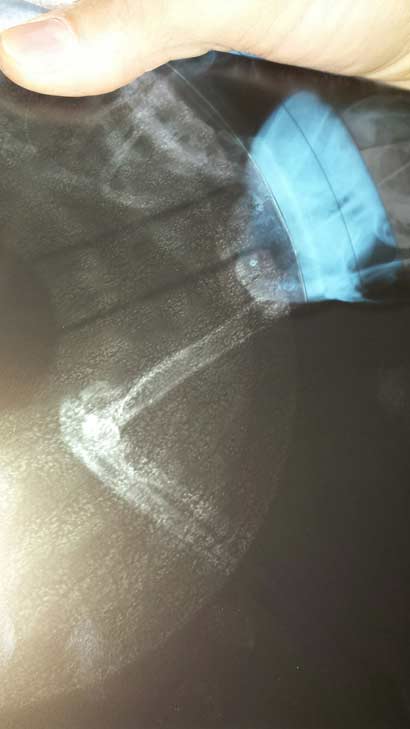

Wir waren mit Gargamel beim Röntgen, leider keine gute Nachricht. Gargarmel hatte vor zig Monaten bereits einen Sturz aus aus hoher Höhe, er hat sich dabei den linken Ellenbogen gebrochen. Kann sein linkes Bein daher nicht mehr durchstrecken und hinkt dadurch.

Der Besitzer hatte wohl nichts unternommen und die Knochen sind falsch zusammen gewachsen, so daß es nun inoperabel ist.